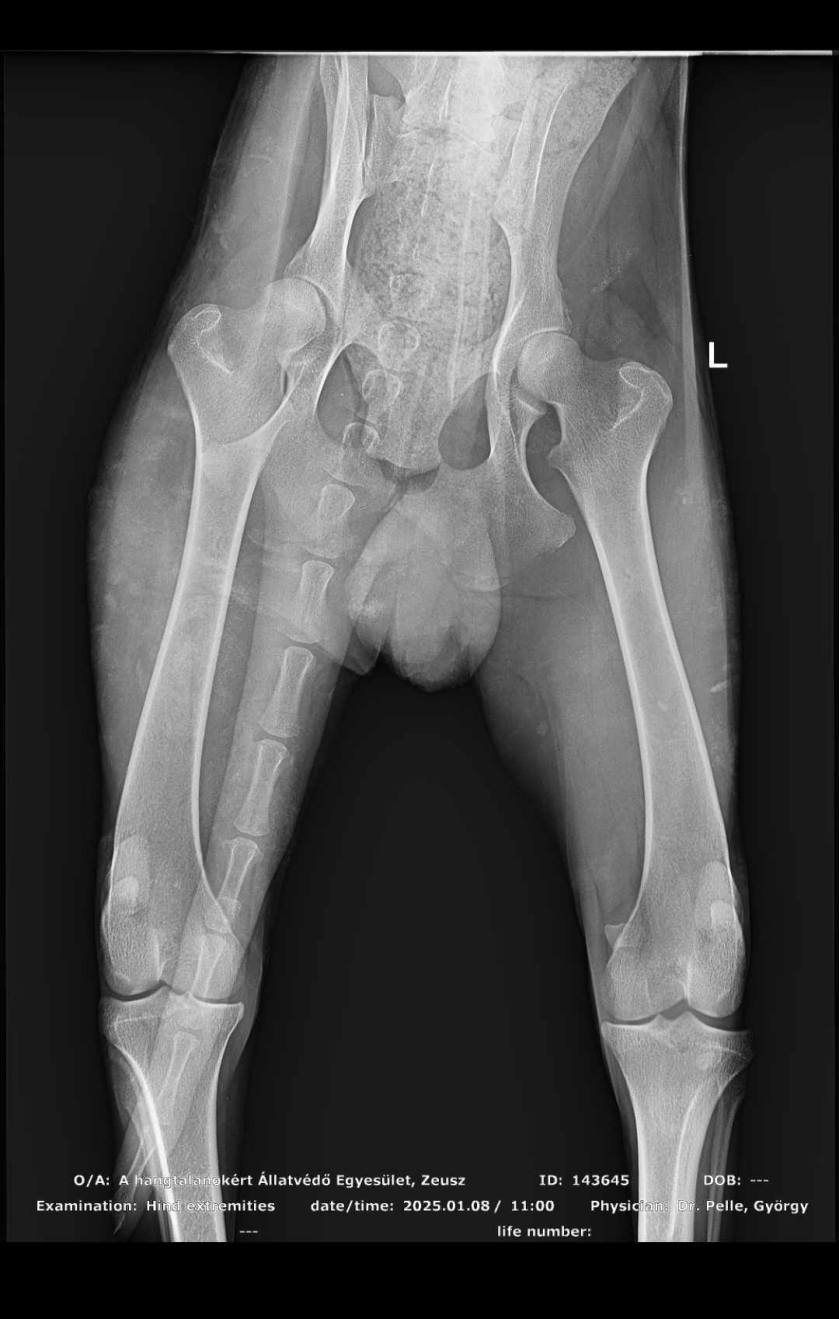

Zeus konnte gestern erfolgreich operiert werden und ist soweit wohlauf. Er bleibt noch unter Beobachtung in der Tierklinik und darf voraussichtlich Montag ins Tierheim.

Ein erneutes Blutbild hat bereits verbesserte Blutwerte ergeben. ![]()

Nun ist das A und O, dass Zeus zunimmt und wieder richtig laufen wird.